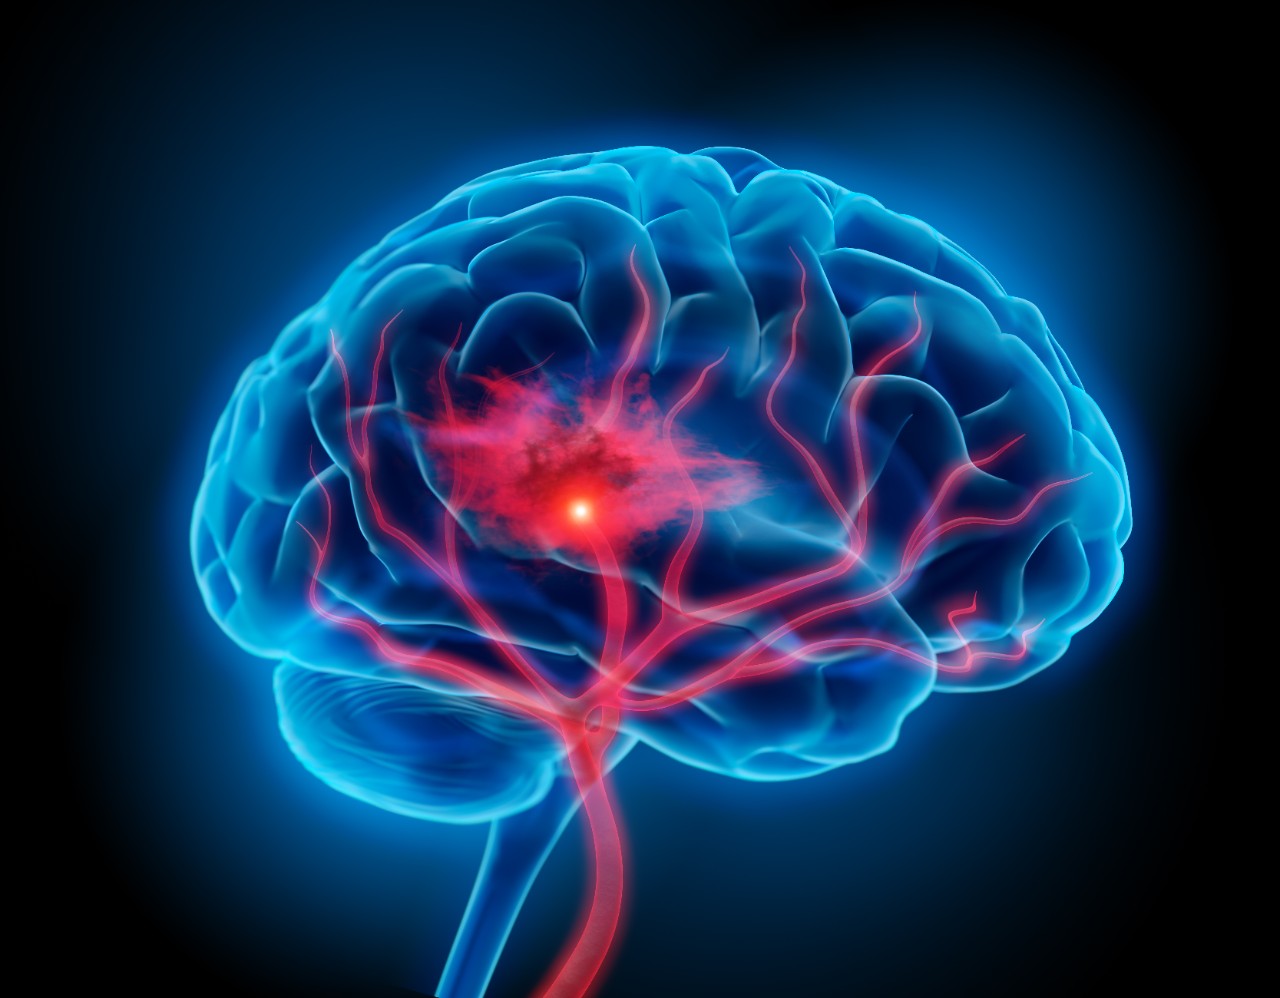

Featured photo at top of illustration of brain with stroke symptoms. Photo/PeterSchreiber.media/iStock.